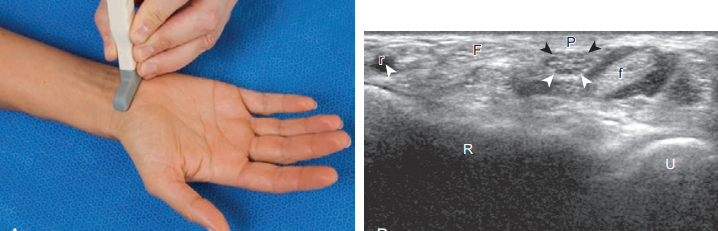

손바닥 쪽에서 먼저 검사할 구조물은 정중신경, 굽힘힘줄, 그리고 손바닥 쪽 손목관절이다. 검사는 구조물의 적절한 위치를 정확하게 알기 위하여 힘줄과 정중신경의 가로면에서 시작한다. 정중신경을 검사하기 위해서는 손목굴 바로 위쪽의 손목주름(wrist crease) 부위에 탐촉자를 가로방향으로 놓는다. 가로면 영상에서 정상 말초신경은 낮은 에코의 신경다발(nerve fascicle)과 신경다발 사이의 높은 에코 결합조직에 의해 벌집모양으로 보인다. 말초신경은 혼합에코로 보이기 때문에, 높은 에코 조직으로 둘러싸인 부위(예를 들면 손목굴)에서는 신경은 상대적으로 낮은 에코로 보이나, 낮은 에코 조직으로 둘러싸인 부위(예를 들면 아래팔)에서는 신경이 상대적으로 높은 에코로 보인다.

손목주름 부위에서 정중신경은, 높은 에코 힘줄과 대비되어 비교적 낮은 에코의 원형 또는 타원형으로 분명하게 보인다. 정중신경을 주위 힘줄로부터 구분하기 힘든 경우에는 탐촉자를 가로방향으로 놓고 몸 쪽(위쪽)으로 이동하면 구분에 도움이 된다.

정중신경은 굽힘힘줄의 안쪽에서 바깥쪽으로 주행하여 얕은 손가락굽힘근과 깊은 손가락굽힘근 사이에 위치한다. 이 부위에서 정중신경주위에는 높은 에코의 결합조직과 지방이 있기 때문에 신경은 상대적으로 낮은 에코로 보인다. 이러한 특징적인 주행방향, 위치, 그리고 에코를 아는 것이 정중신경을 구분하는데 도움이 된다. 다음에는 탐촉자를 손목굴 방향을 향해 아래쪽으로 이동하여 손목주름 부위에서 정중신경의 단면적 측정한다(구조물의 둘레를 측정하는 기능이 있다면 그것을 이용함). 손목주름 부위의 가로영상에서 정중신경과 굽힘힘줄을 구분하는 다른 방법으로는 탐촉자를 힘줄에 대해 비스듬하게 기울여 보는 것이다. 비등방성(anisotropy)때문에 힘줄은 높은 에코에서 낮은 에코로 바뀌는 반면 낮은 에코의 정중신경은 변화가 없다.